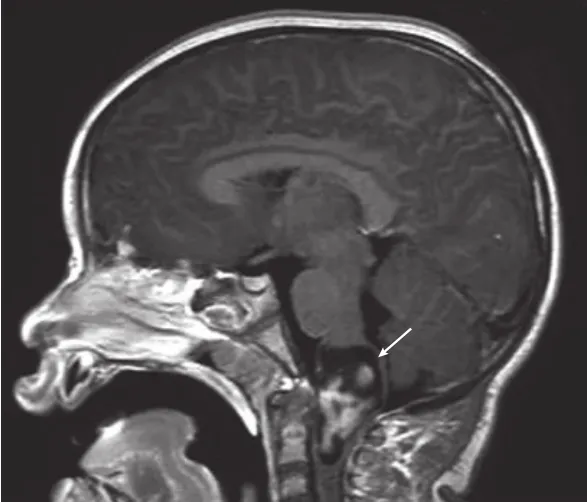

在MRI上,大多數(shù)延髓-頸髓膠質(zhì)瘤白質(zhì)呈低信號。在T2和質(zhì)子密度圖像上,白質(zhì)呈高信號(圖1)。在矢狀位MRI上,延髓-頸髓膠質(zhì)瘤從延髓的尾部三分之二延伸到延髓-頸髓的喙側(cè)。它們往往會(huì)在造影劑給藥后迅速強(qiáng)化。

圖1

圖1:一名6歲女孩的矢狀位MRI顯示強(qiáng)化的延髓-頸髓交界處的病變(箭頭)。這個(gè)孩子最初表現(xiàn)為癲癇發(fā)作,但后來表現(xiàn)出進(jìn)行性左側(cè)偏癱。